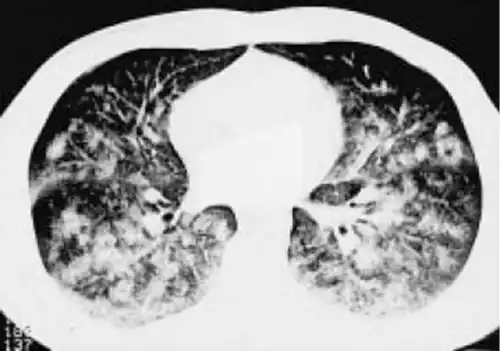

Nevertheless, deep depths apparently create intrathoracic pressures lower than the ambient pressure and thus pulmonary barotrauma can develop during the descent. Among BH divers, this barotrauma has been termed lung squeeze, which is not uncommon [] and is accompanied by pulmonary edema and hemorrhage that can be exhibited by ultrasound [, ] and computed tomography [] (Fig. 2).

Fig. 2

Thoracic computed tomography. Disseminated alveolar opacification after a BH deep dive. Reproduced with permission from the European Respiratory Society© European Respiratory Journal [].